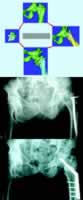

本报讯 近日,仁济医院骨科张继东副教授等为1例56岁男性患者实施了计算机辅助股骨粗隆间截骨手术。

该患者7年前因外伤致股骨粗隆间骨折,于当地医院手术治疗后畸形愈合。患侧肢体短缩4.5 cm。张继东副教授与上海交通大学国家数字化制造技术中心合作,结合医学影像技术、计算机技术和快速成形技术,通过图像处理、虚拟现实,建立股骨及骨盆模型,精确定量,设计个性化截骨方案,同时进行截骨矫形手术的设计、干预和评价(如图)。最后选择最佳的治疗方案,成功地为患者实施了截骨矫形手术。术后,患者两侧下肢基本恢复正常(患侧比健侧短缩1.0 cm)。, http://www.100md.com